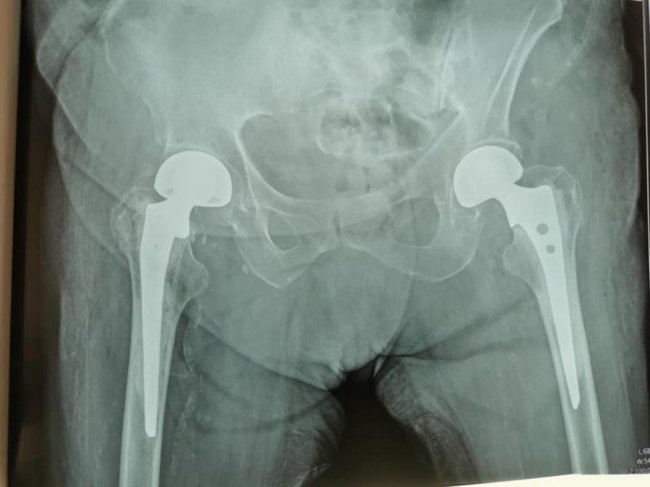

У луцькій лікарні 95-річній жінці замінили суглоби. ФОТО

У Луцькій міській клінічній лікарні у відділенні травматології та ортопедії провели два ендопротезування (заміну суглобів) 95-річній пацієнтці.

8 серпня цього року у відділення поступила пацієнтка, 1926 року народження, з переломом шийки лівої стегнової кістки. Пацієнтці провели біполярне ендопротезування цього стегна.

"Цікаво, що у грудні 2020 року вона поступала до нас з аналогічним переломом шийки правої стегнової кістки, - розповідає завідувач відділення Тарас Куровець, - тоді теж було проведено біполярне ендопротезування. Хвора гарно відновилася після травми. Ходила вже без палочки. І ось знову травма вже іншої ноги. Для старших людей, а тим більше для 95 років, це значна травматизація і єдиний вихід - це ендопротезування", - пишуть у дописі.